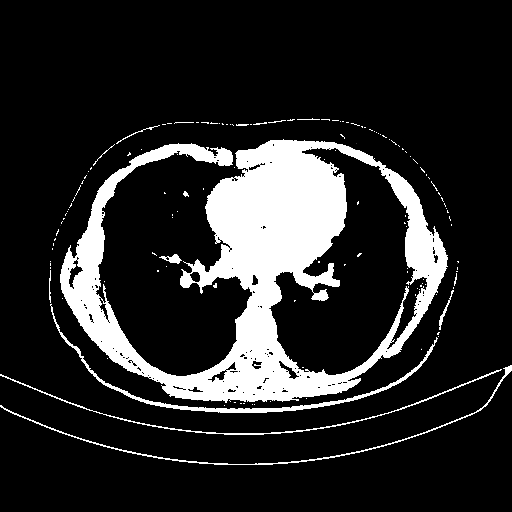

Generated VENOUS CT scan (A→B translation)

Full window (WL 1023.5, WW 4095 β†’ Low βˆ’1024, High +3071)

Actual HU range: [-1024.0, 3071.0]